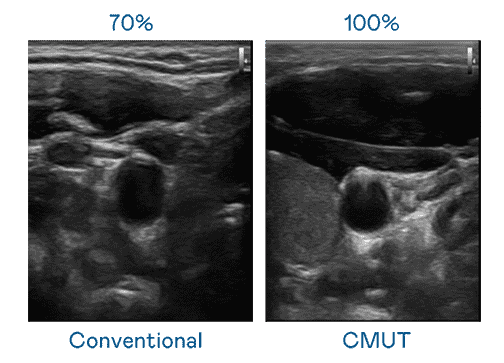

CMUT 技术是一种用电容式微机电元件来产生超音波讯号的技术。。。。与传统 PZT 压电式技术相比,,,,CMUT 频宽增加 30%,,更宽频的超音波讯号让影像解析度大幅提升,,,是实现高影像品质医疗超音波扫描、、、、促进精准医疗发展的关键技术。。。

大频宽带来超清晰影像

超音波影像的解析度高低,,,,首先取决于探头能发出的讯号频宽。。william威廉中文官网 CMUT 可提供高清晰的超音波讯号,,,,提供高频宽、、、、高灵敏度、、影像纹理细节更高的超音波影像,,协助医护人员缩短影像判读时间及利用精准的医疗影像进行诊断。。。。